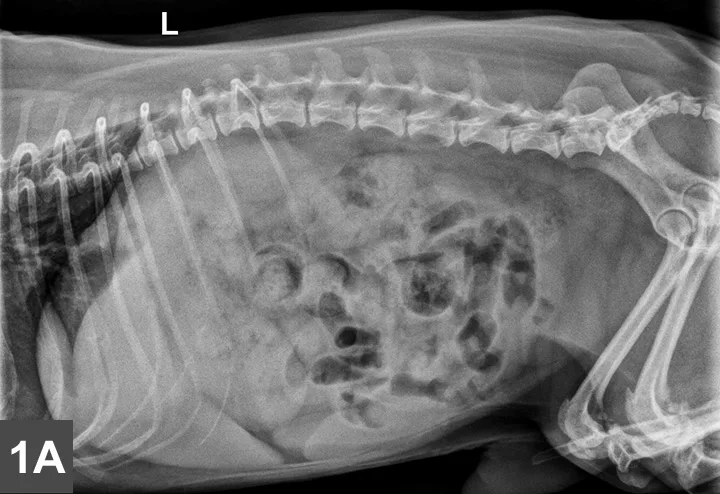

Left lateral (Figure 1A) and VD (Figure 1B) radiographs of the abdomen were obtained. Although thoracic radiographs were also taken, the findings were considered normal and, therefore, are not included here.

Figure 1A & B

Left lateral (Figure 1A) and VD (Figure 1B) views of the abdomen.

Radiographic Findings

A mottled mineral opacity measuring ~12 mm in diameter is seen just caudal to the last right rib in the VD view, near the pyloroduodenal junction (Figure 2B, black arrows), and superimposed over the pylorus in the lateral view (Figure 2A, black arrows). This opacity could be a foreign body or a mineralized mass or lymph node. Heterogeneous soft tissue material, compatible with ingesta, is present in the gastric lumen as well as throughout the intestines, but no abnormal distention is evident. The liver extends past the costal arch with mild caudal displacement of the gastric axis, consistent with mild hepatomegaly; the margins are smooth. The remaining viscera and serosal detail are normal.